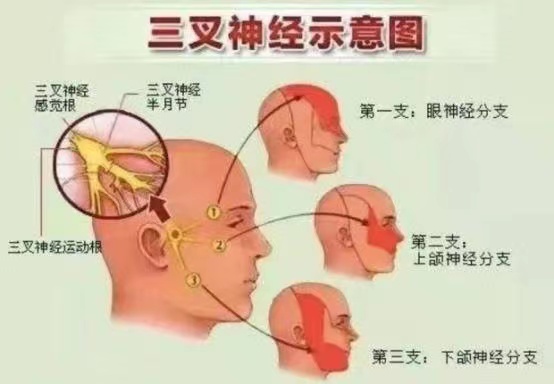

三叉神经痛是最常见的脑神经疾病,以一侧面部三叉神经分布区内反复发作的阵发性剧烈疼痛为主要表现,多发生于中老年人,女性多于男性。

三叉神经痛,有多痛?该病发作时一般分布在面部三叉神经内,据患者形容,发病时“骤发、骤停,像闪电样、刀割样、灼烧样……同时还会伴有面部肌肉的痉挛,会面红、流泪,连说话、洗脸、刷牙、走路都能导致剧烈疼痛”。这种疼痛,就像不定时炸弹随时可能爆发,频繁发作,严重影响工作生活。

三叉神经球囊压迫术是一种微创治疗,手术基本方法为从面部皮肤穿刺达到三叉神经出颅腔的部位,以球囊导管置入麦克氏囊,通过球囊扩张适度压迫三叉神经半月节,目的是卡压三叉神经的痛觉纤维并最大程度保留触觉纤维的功能。